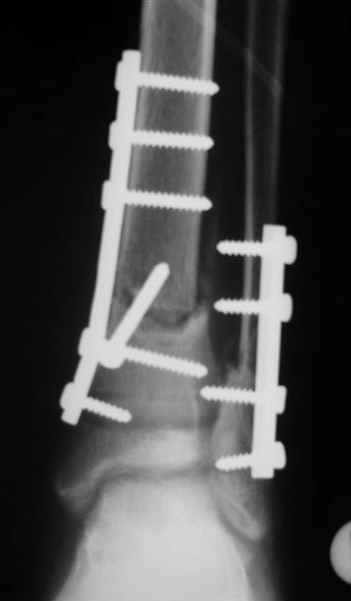

Evgueny Tchekashkine 31 Март 2005, 00:45

Уважаемый Виталий Евгеньевич,

Помятуя наш недавний разговор о фиксации м.б. кост, высылаю послеоперационные картинки..

Напомню- разбирали случай 17 летнего молодого человека перелом дист тиб.фиб. хирургия после 3 недель с момента травмы( безуспешные попытки закрытой репозиции) Раны заживают первичным натяжением, занимается физиотерапией, пока никаких проблем не наблюдается

Как ты тут оцениваешь восстановление оси большеберцовой кости?

Является ли рутинной практикой у вас использовать снимок противоположной конечности как шаблон для измерения осевых отклонений?

Отправитель: Evgueny Tchekashkine 01 Апрель 2005, 22:45

Согласный я с тобой:-)) есть остаточная вальгусная деформация (по снимку видно перекрывание дист. фрагментом б.б по латеральной поверхности проксимальноо фагмента на 2-3 мм и наружная лодыжка репонирована с укорочением, судя по прямой проекции. Необходимость использования интраоперационно дистрактора была бы оправдана (вручную было непросто *вытянуть* дистальный отломок.)